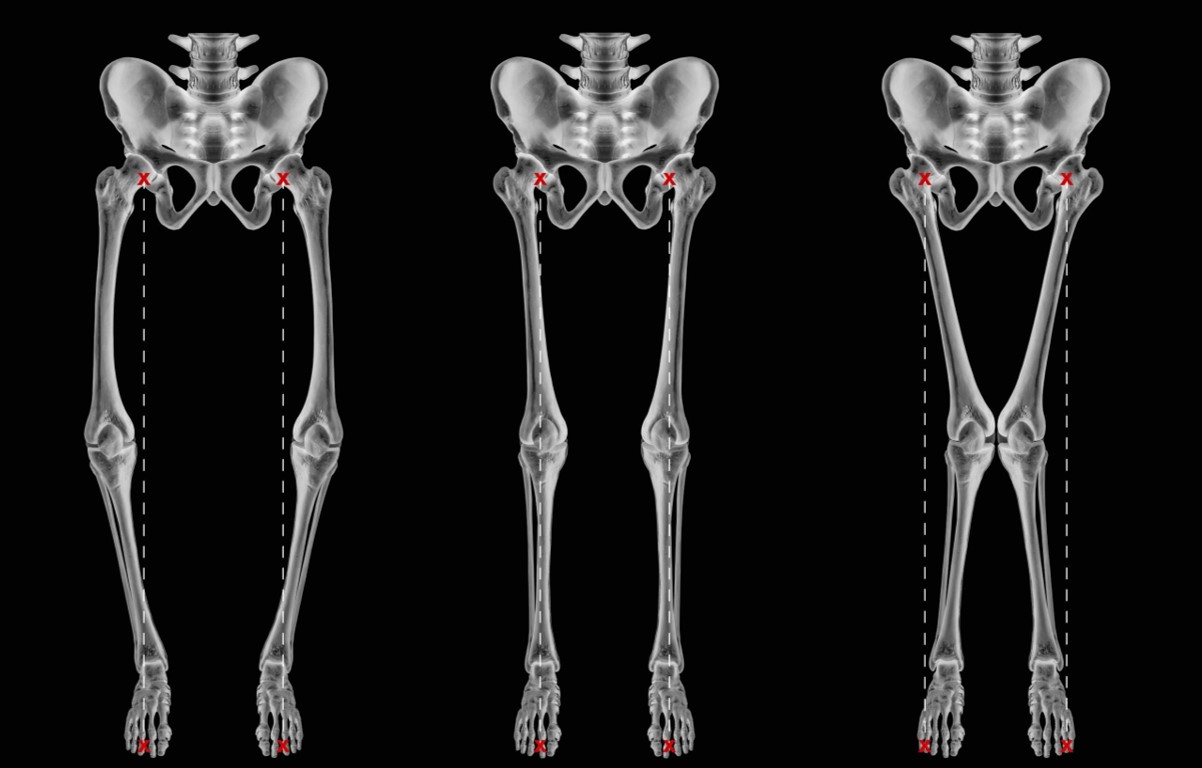

Dentro de las deformidades angulares de los miembros inferiores, las dos más frecuentes conocidas como genu varo y genu valgo, son alteraciones al mirar las piernas de frente donde vemos las piernas torcidas.

Genu Varo: Hace referencia a cuando las piernas están arqueadas, es decir, las rodillas se separan una de la otra. La pierna tiene forma de C o de paréntesis.

Genu Valgo: Es lo contrario, las piernas se cruzan como si las rodillas fueran a tocarse, son las piernas en forma de X.